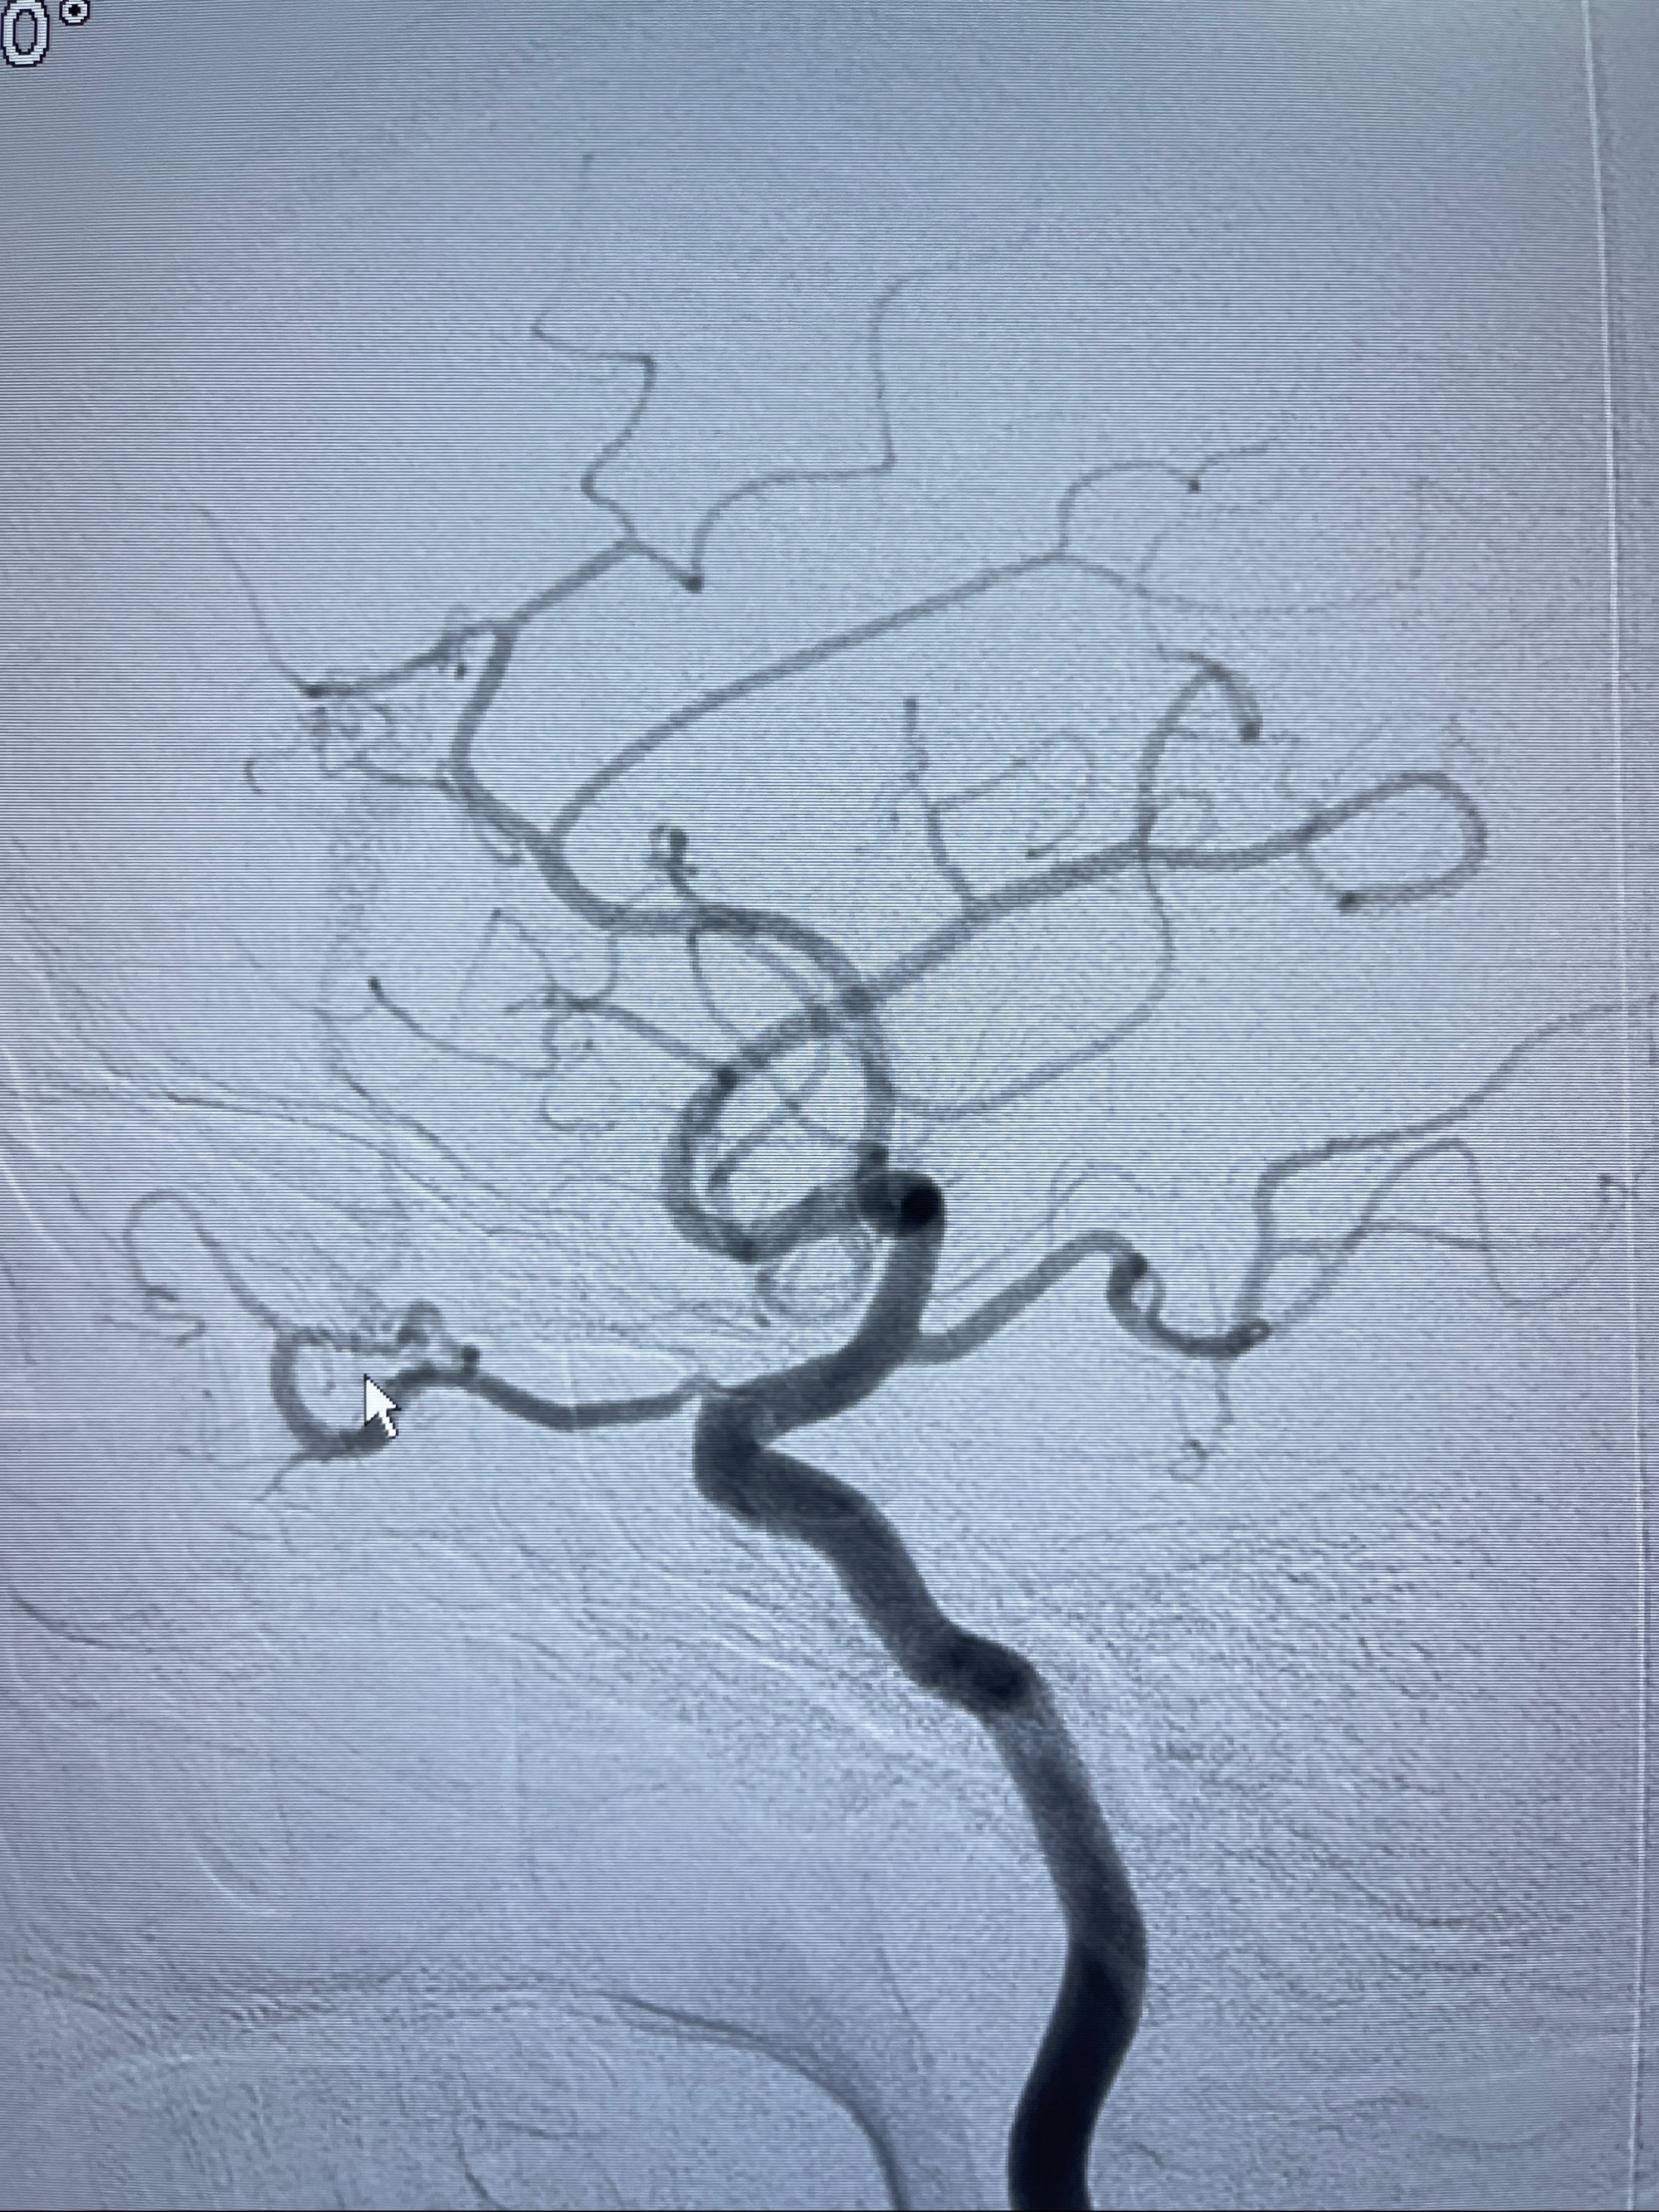

2023年8月21日]景德镇市第一人民医院脑血管造影检查,提示:主动脉弓、双侧颈总动脉、锁骨下动脉造影未见异常,左侧大脑前动脉静脉瘘。

2023-09-13全脑血管造影:前颅底硬脑膜动静脉瘘,供血动脉为双侧胼周动脉、眼动脉脑膜支,静脉向上矢状窦方向引流

- 介入干预:静脉途径栓塞or动脉途径填塞?